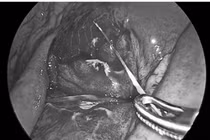

di-vat-1.jpg

Nội soi lấy dị vật xương cá cho bệnh nhân - Ảnh BVCC

Qua thăm khám và nội soi Tai Mũi Họng, bác sĩ phát hiện dị vật là một mảnh xương đầu cá lớn (khoảng 4 x 1,5 cm) mắc tại vùng hạ họng, đầu xương cắm vào thành sau họng – vị trí sâu, tiềm ẩn nhiều nguy cơ biến chứng.

Bệnh nhân đã được lấy dị vật an toàn. Đây là trường hợp có nguy cơ cao do kích thước dị vật lớn, cắm sâu, nếu chậm trễ hoặc xử trí sai cách có thể dẫn đến hậu quả nghiêm trọng.